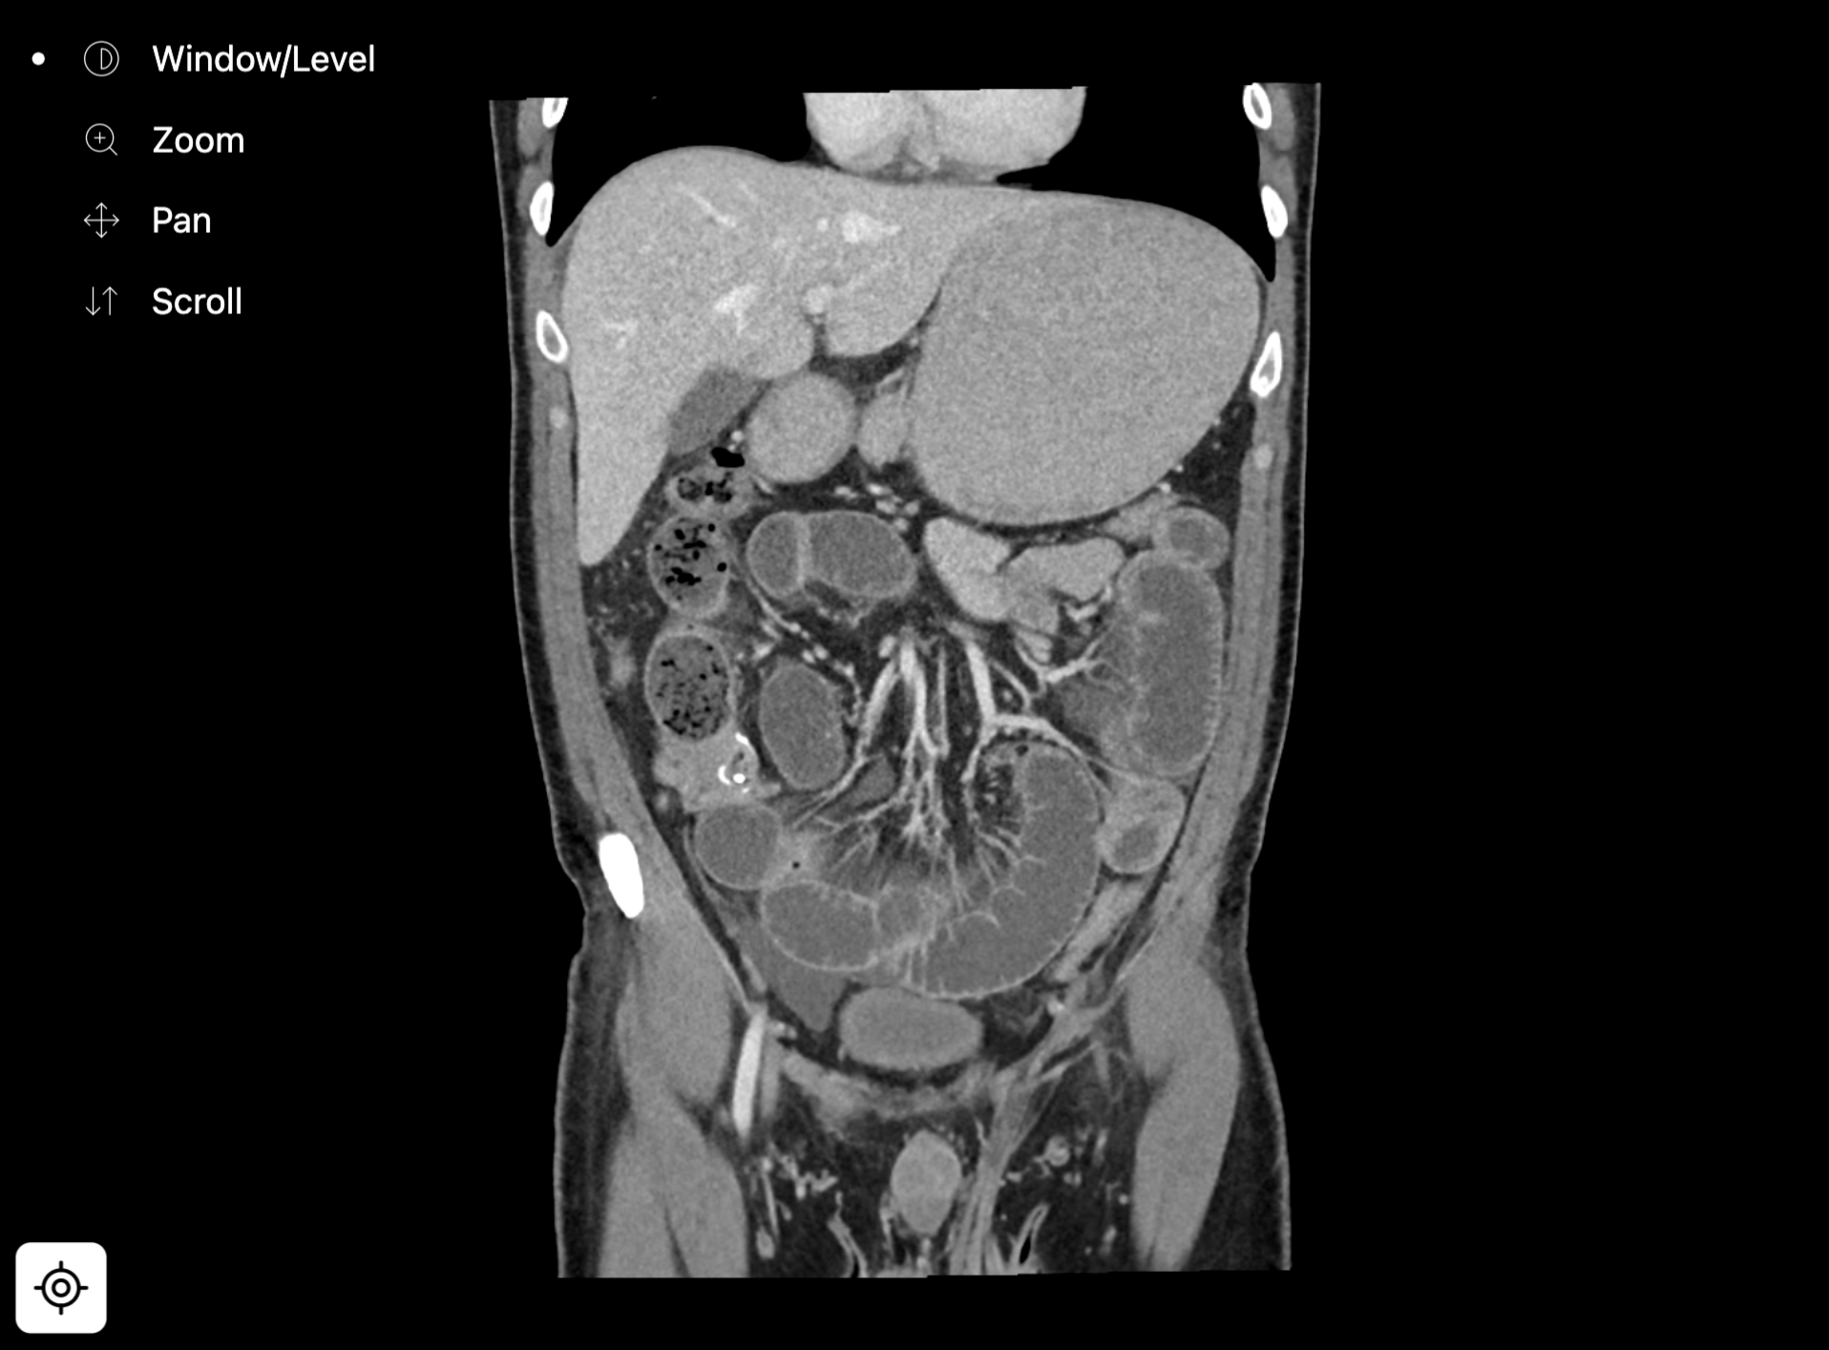

Small bowel obstruction with transition point at the anastamosis